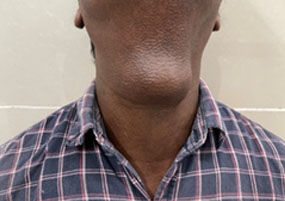

TDC is the most common congenital anomaly related to the thyroid gland. In a TDC, papillary carcinomas typically present as swellings along the midline of the neck, which move with deglutition and tongue projection. Less than 1% lof all TDC cases present with papillary carcinomas. This type of pathology has a good prognosis and can be successfully managed with cyst removal (Sistrunk procedure) and careful follow-up. Thyroidectomy, neck lymph node dissection, or adjuvant treatments are not required in most cases.